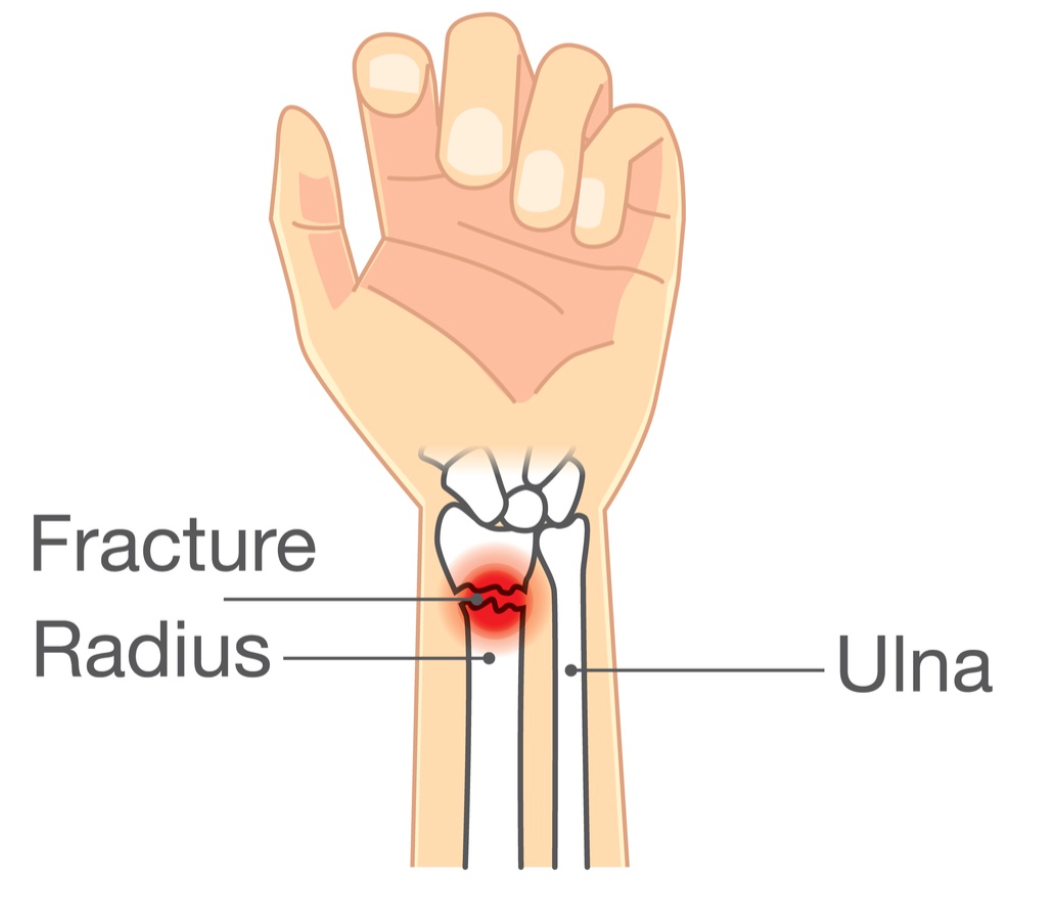

桡骨远端骨折手术修复后有目的的活动的重要性

作者:Kelsey Melton Collis, JM、Mayland, EC、Wright-St Clair, V.、Rashid, U.、Kayes, N. 和 Signal, N.(2022)。手腕和前臂的评估...

老年患者桡骨远端骨折掌侧锁定钢板接骨后的早期活动:随机对照试验

作者:Rachel Reed Sørensen, TJ、Ohrt-Nissen, S.、Ardensø, KV、Laier, GH 和 Mallet, SK (2020)。掌侧锁定钢板后早期活动...

使用压缩手套治疗桡骨远端骨折

使用压缩手套治疗桡骨远端骨折 Miller-Shahabar, I.、Schreuer, N.、Katsevman, H.、Bernfeld, B.、Cons, A.、Raisman, Y. 和 Milman, U. (2018)。功效...

肥胖或吸烟会改变桡骨远端骨折的结果吗

Hall, Matthew J.、Ostergaard, P.、Dowlatshahi, A.、Harper, C.、Earp, B. Rozental, T. (2019)。肥胖和吸烟对掌侧钢板术后结果的影响......